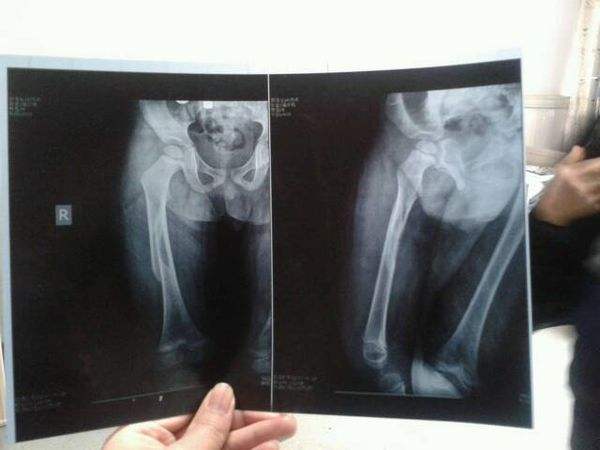

肿胀期过后,肿胀逐步消退,会引起松动,固定就不牢固,需要重新固定。否则骨折端松动,容易引起重新移位。消肿后,孩子重新固定,需要重新拍片,确定骨折端位置良好的话,孩子可以不抬高上肢,可以带着石膏玩耍。拆石膏需要再次拍片,确定骨折已经愈合,才可以拆除。有的孩子骨折长得快,有的难一些,不同部位的骨折,生长速度也不一样。所以是否愈合了,要以拍片为准!太过肿胀的情况下,打了石膏最好在医院里观察。等肿胀高峰过后再回家,比较安全。